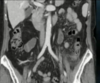

TOMOGRAFIA DE ABDOMEN COM CONSTRASTE VENOSO .

MASSA RETROPERITONEAL A DIREITA QUE COMPRIME AS VISCERAS A DIREITA , A QUAL NÃO INVADE AS ESTRUTURAS. PRESENÇA DE CAPTAÇÃO HETEROGENEA DO CONSTRASTE NA PERIFERIA

ASPECTO DE SARCOMA PERITONEAL.